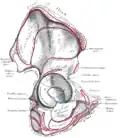

Rechtes Hüftbein. Innere Oberfläche -

Linkes Hüftgelenk, Sicht auf die Ebene der Hüftgelenkspfanne vom Becken innen